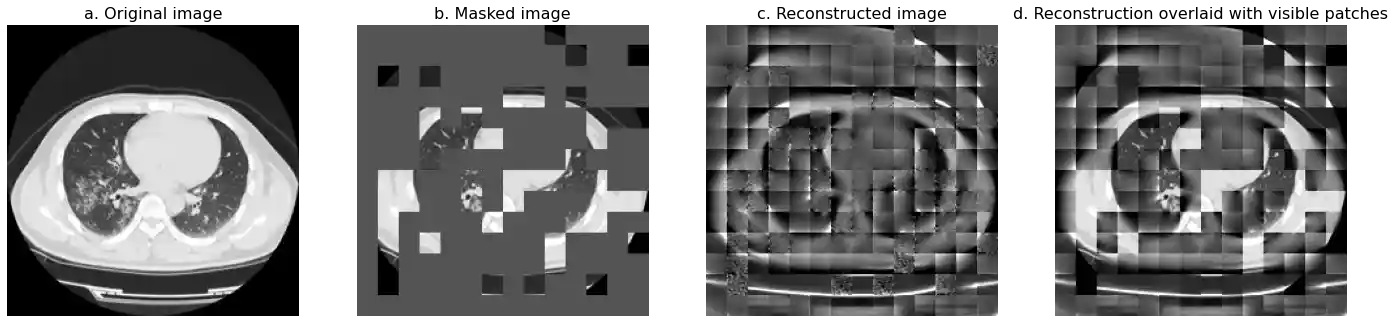

Demo of Visual Reconsruction by MAE in Medical Images

Visual Reconsruction of MAE-B/16_DATA14 Visual Reconsruction of MAE-B/16_C1000Transitional training scheme